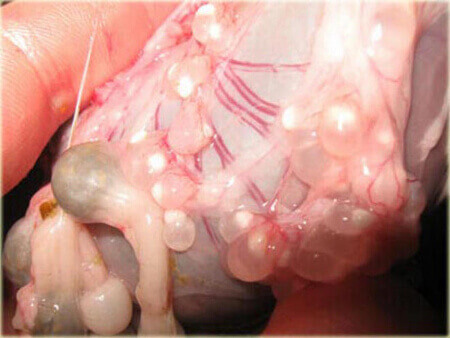

Además, pueden incluso destruir un cuerpo que parece joven y saludable. Yo diría que las muertes causadas por parásitos representan el 85 % de todas las muertes inesperadas o llamadas "súbitas". Mire estas fotos realizadas en nuestro laboratorio:

Un páncreas paralizado por parásitos (fue extirpado completamente durante la cirugía):